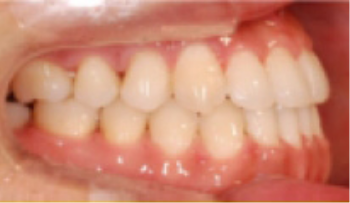

교정 치료 Before&After

• 상악 전돌(돌출) 위턱이 앞으로 나옴.

Before

After